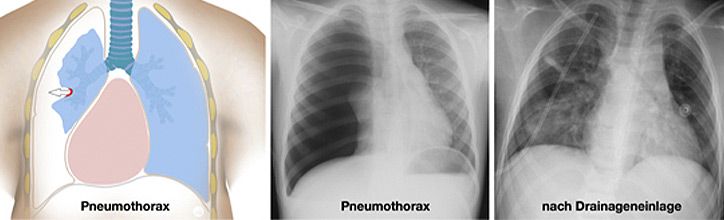

Verletzungen im Brustkorb

Thoraxtraumen betreffen sowohl den Weichteilmantel, das knöcherne Skelett (Rippen, Wirbelsäule) als auch die intrathorakalen Organe (V.a. Lunge, aber auch Speiseröhre, das Zwerchfell, die großen Gefäße und das Herz). Die Verletzungen können durch Verbrennungen entstehen, durch Verschlucken von Fremdkörpern oder giftiger Flüssigkeiten sowie durch stumpfe oder seltener spitze Gewalt. Beim eigentlichen Thoraxtrauma sind die inneren Organe betroffen, wobei es sich um ein schweres Krankheitsbild handelt, welches im Kindesalter dennoch in der Regel konservativ zu therapieren ist.

Grundlegender Unterschied beim Kind verglichen mit dem Erwachsenen, ist die geringere Körpergröße und Masse sowie die hohe Plastizität der knorpeligen Rippen. Diese frakturieren (brechen) beim stumpfen Thoraxtrauma in der Regel nicht, leiten aber die Kraft der Gewalteinwirkung vielmehr auf die darunter liegenden Strukturen fort. Folge können Gewebezerreissungen der Lungenstrukturen sein mit der Folge von Blutungen, Ödembildung, Pneumo- oder Hämatothorax (Abbildung)